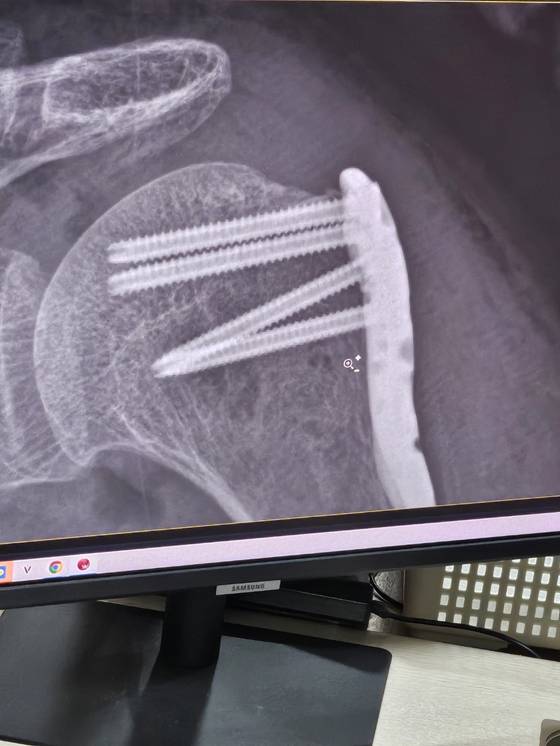

백씨는 이날 저녁 8시 반쯤 수인분당선 열차에서 내려 지하철 2호선으로 갈아타기 위해 왕십리역 환승 통로를 걸어가던 중이었습니다. 백씨는 "마주보며 걸어오던 남성이 아무 말도 없이 갑자기 때렸다"면서 "어깨를 먼저 때리고, 아파서 몸을 굽히자 허리 등도 때렸다"고 당시 상황을 설명했습니다. 행인의 신고로 병원에 실려 간 백씨는 어깨뼈가 부러지고 탈골됐다는 진단을 받고 어깨에 철심을 넣는 수술을 받았습니다. 백씨는 몸 곳곳에 피멍이 든 사진도 취재진에게 보내왔습니다. 백씨 가족은 CCTV부터 확보하고자 했습니다. 왕십리역은 지하철 4개 호선이 지나갑니다. 코레일이 관리하는 수인분당선과 경의중앙선 그리고 서울교통공사가 관리하는 지하철 2호선과 5호선입니다. 백 씨 가족이 양 쪽에 CCTV를 요청했습니다. 돌아온 답은 같았습니다. "환승 통로라 CCTV가 없다"